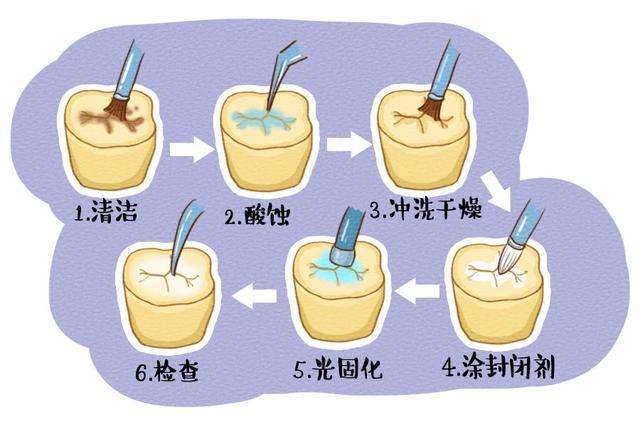

牙齿龋坏了,长了牙洞,及时修补,才能避免更多的口腔问题出现。但据了解,很多小孩对补牙都十分抗拒,因为他们对补牙的过程并不了解。其实,在细菌没到达神经的情况下,补牙是不会疼的,而补牙的步骤主要有以下四点:

2.制备窝洞

3.消毒窝洞

4.充填

这是补牙的较后一步,将准备好的补牙材料,填入到制备好的窝洞里面,调整好形态之后,就使用蓝光固化。